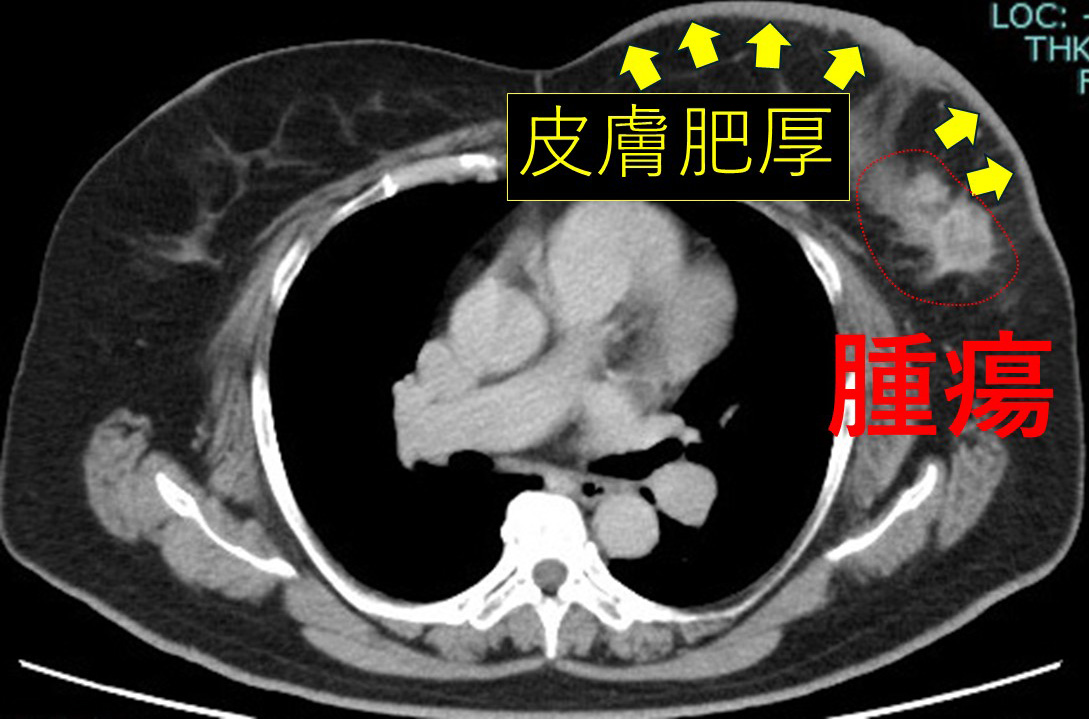

術前抗がん剤後 腫瘍著明に改善 皮膚浮腫の範囲も縮小

リンパ節も、かなり効いています。

と、いうことで結局当院へ転院術前抗がん剤(phesgo+docetaxel)を施行してつい最近手術しました。

患者さんは結構な遠方(中京地方)でしたが、自家用車で外来ケモ通い切りました。(その思いに拍手!)

効いたねー!